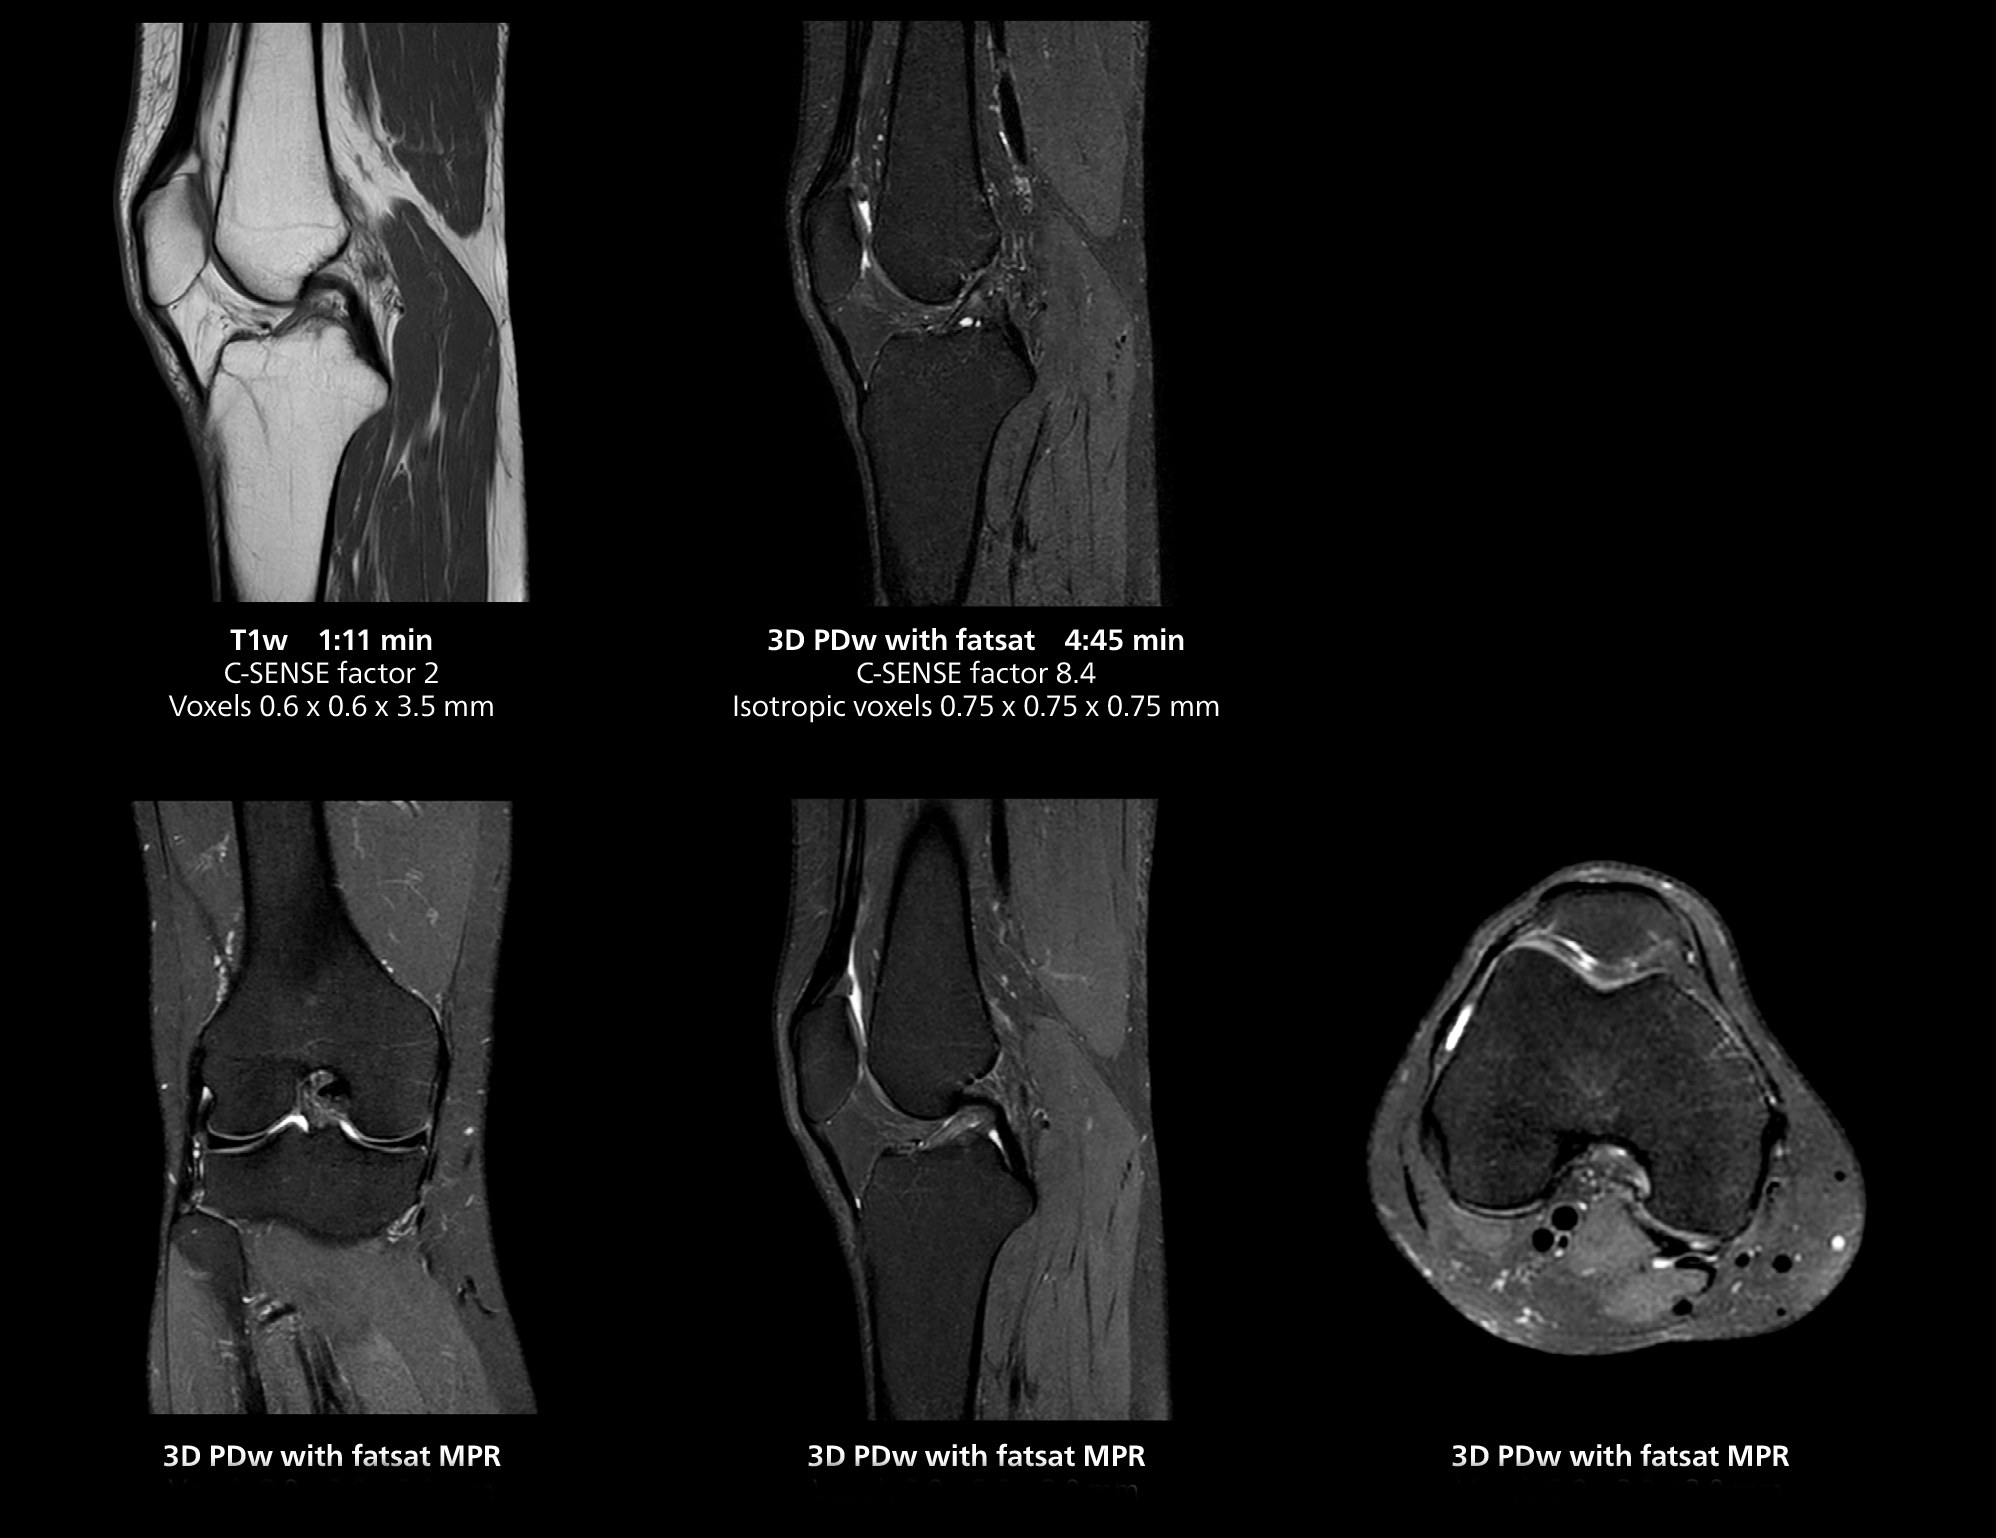

3D knee imaging

The isotropic high resolution 3D sequence in this MRI case allows for reformatting to obtain other orientations with high quality. Acquired on the MR 5300 system.

3D knee imaging

The isotropic high resolution 3D sequence in this MRI case allows for reformatting to obtain other orientations with high quality. Acquired on the MR 5300 system.

The MR 5300 with Compressed SENSE is up to 50%** faster for many exams. It can provide routine exams in less than 5 minutes and whole-body exams in less than 20 minutes. Saint-Augustin has taken advantage of that speed to create highly efficient protocols. The hospital’s standard stroke protocol is just about 8 minutes, and standard ENT, prostate PIRADS staging, and endometriosis studies all clock in at just about 10 minutes.***

“We have more speed in 3D sequences,” Dr. Gellée states. “With Compressed SENSE, we can replace two or three 2D scans withone high-quality 3D scan. High quality additional orientations are then obtained by post-processing of the 3D data set, thus saving scanning time.”